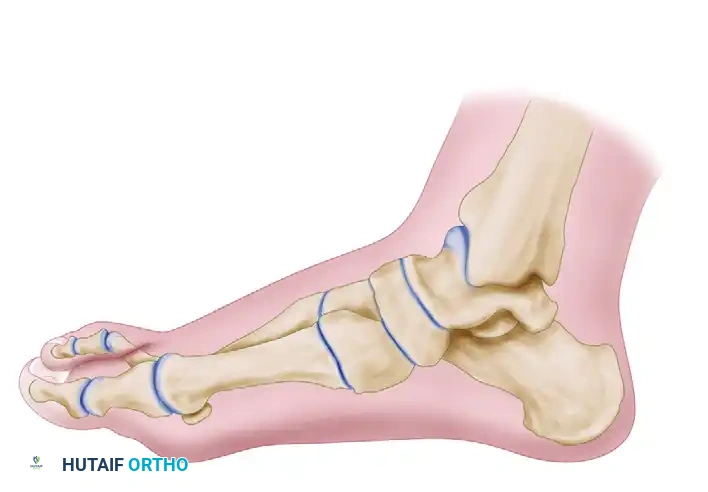

The primary biomechanical objective of the Lapidus procedure is to restore the weight-bearing capacity of the medial column. In patients with first ray hypermobility, the first metatarsal dorsiflexes and inverts during the terminal stance phase of gait, leading to a loss of the windlass mechanism and subsequent transfer of load to the lesser metatarsals (transfer metatarsalgia). By achieving a rigid arthrodesis at the first TMT joint, the surgeon effectively stabilizes the medial column, allowing for powerful correction of the intermetatarsal angle (IMA) while simultaneously plantarflexing the first ray to restore normal forefoot contact pressures.

Clinical Pearl: The Lapidus procedure is not merely a uniplanar correction. It is a triplanar realignment. The first metatarsal must be adducted (to close the IMA), plantarflexed (to restore medial column weight-bearing), and derotated (to correct the frontal plane pronation of the first ray).